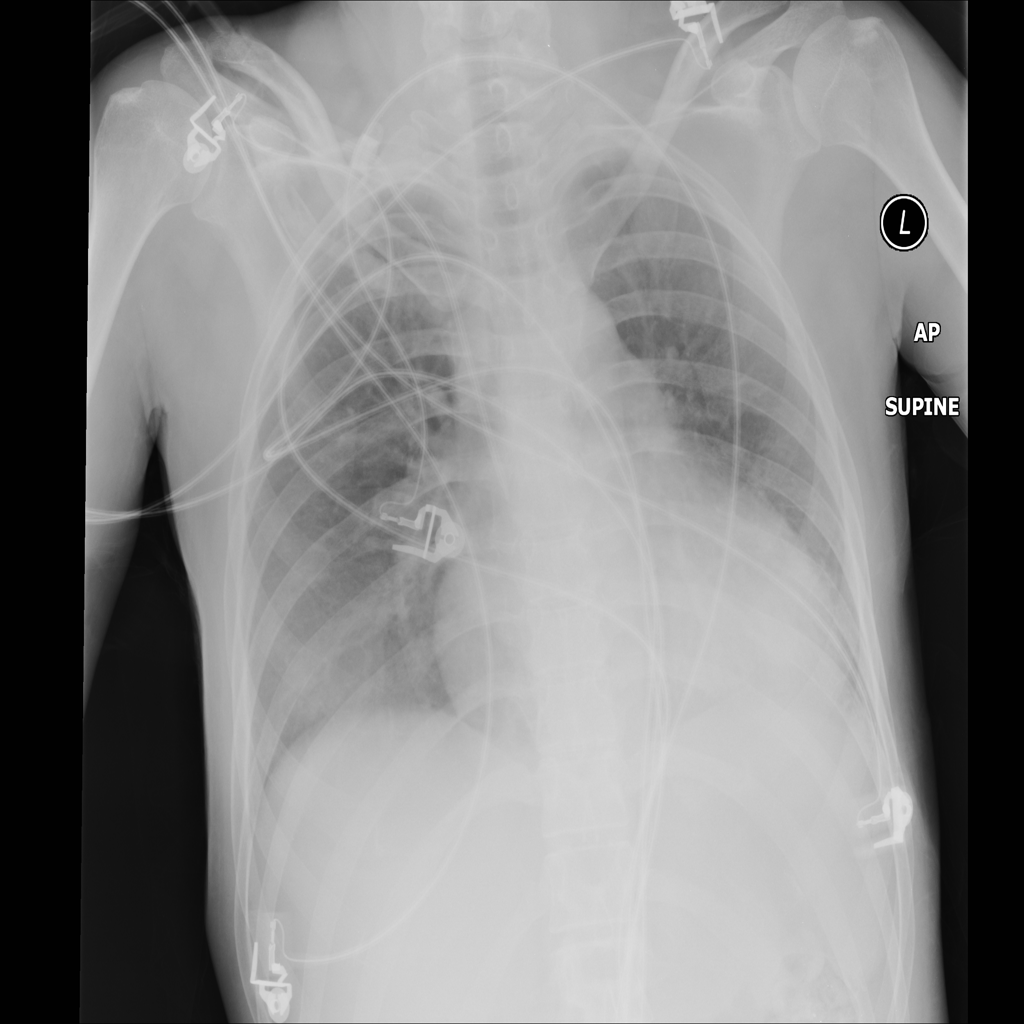

PAT-A1E2 · IMG-001Pneumonia

PAT-A1E2 · IMG-001

AP